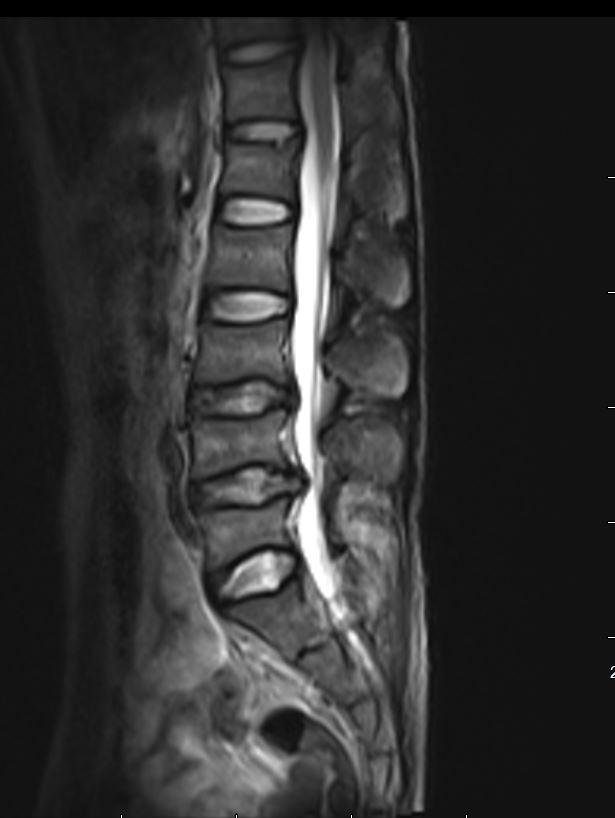

“核磁显示,患者第4、5节腰椎的椎间盘突出严重,髓核已经脱垂至椎管内,严重压迫着神经根,需手术治疗。”接诊的骨科主任医师朱迪说。